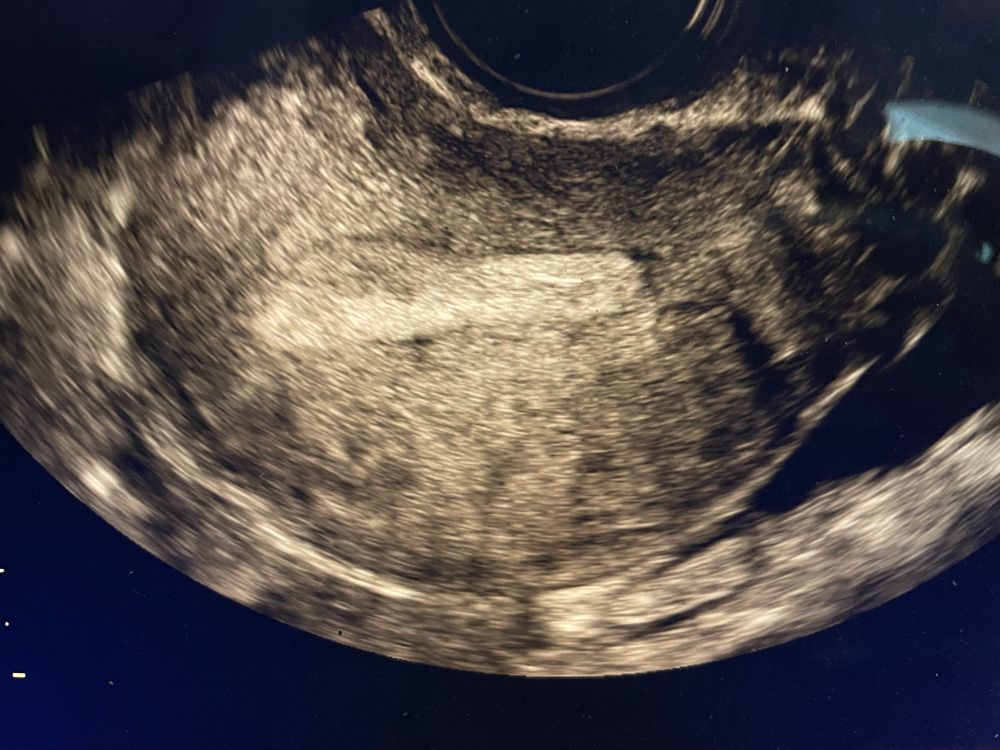

Девочки что это может быть на узи в эндометрии?

Счастье очень близко , у меня неделю назад было эко! Уж полип бы точно заметили. Эта Белая полоска на узи всё эндометрий, во второй фазе он становится белым и монолитным от прогестерона. Я проверяю почти каждый цикл, но вот такого темного места раньше не видела. Спрашиваю о нём

Жидкость в полости матки Эх девочки, расстроеная я капец конечно